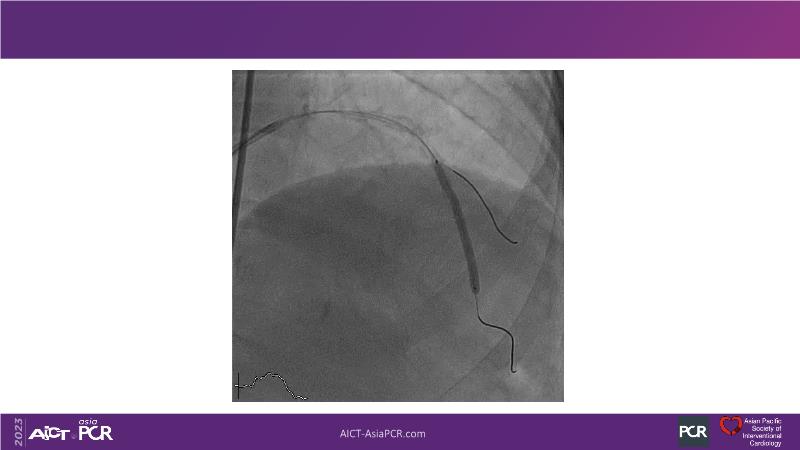

This session is recommended for you if you are seeking insights into the advantages of using IVUS imaging over visual assessment for better outcomes in left main bifurcation procedures. Discuss with experts the benefits of using RotaCUT in lesion preparation for left main bifurcation and explore the impact of high radial strength stents on the procedure's success.

• To see advantages of RotaCUT as part of lesion preparation in left main bifurcation